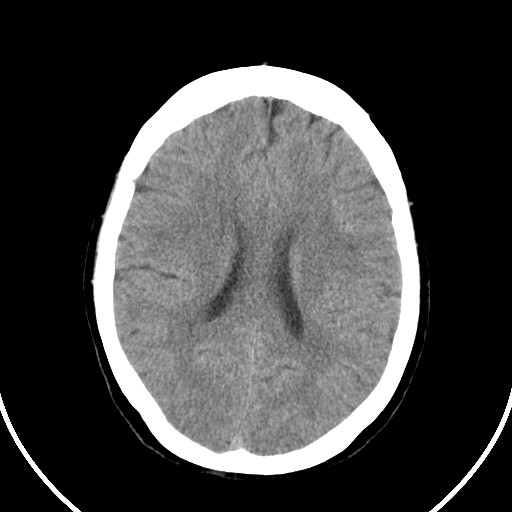

女,56岁,右中指淤肿,右手麻痹1天

右侧侧脑室旁脑白质腔隙性脑梗死。

右侧基底节多发小梗塞

作者: huangyinshan    时间: 2009-8-25 15:37

右基底结区腔梗

右侧基底节区腔隙性脑梗塞

右侧基底节多发腔梗!

双侧侧脑室额角旁对称性略低密度影,边缘模糊,无占位效应,考虑轻度脑白质稀疏症(病人有高血压吗).,右枕叶低密度影多为伪影,不放心薄扫一下.

考虑脑白质病。

考虑脑白质病